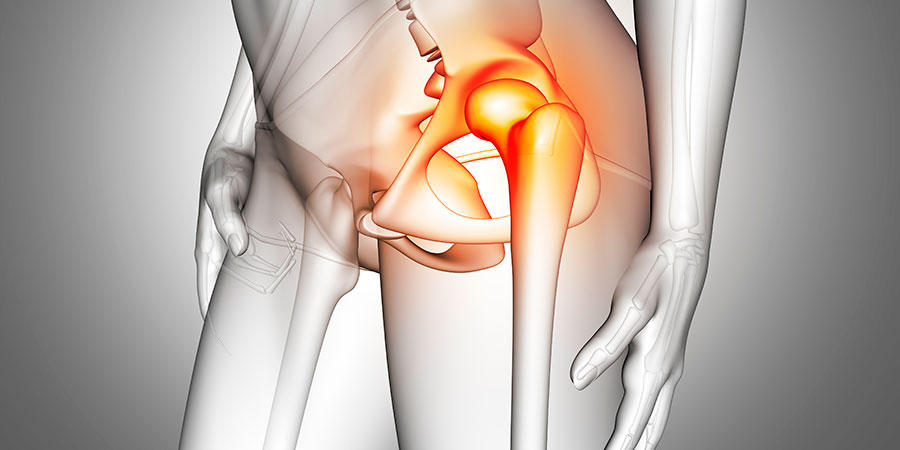

أعراض كسر الورك

من الأعراض البارزة لكسر الورك، الشعور بألم حاد في منطقة الورك أو الأُربية قد يمتد إلى الفخذ أو أسفل الساق. في الغالب، يكون الألم شديدًا وغير قابل للتحمل، ما يمنع المريض من القدرة على المشي أو التحرك بسهولة. في بعض الحالات، يعاني الشخص من صعوبة في تحريك ساقه المصابة، أو قد تكون الساق المتأثرة أقصر من الساق السليمة.

أما في حالة كسر الورك، يشعر الشخص بألم شديد يمنعه من الوقوف أو المشي. هذا الألم قد يترافق مع تشوه أو تقوس في الساق المصابة نتيجة للكسر، بينما لا يحدث هذا في حالات الإصابات الأخرى.

قد يلاحظ المريض أو من حوله أن الساق المصابة تكون موجهة نحو الخارج أو مائلة بزاوية غير طبيعية، ما يشير إلى كسر في الورك. هذا التغير في وضع الساق لا يحدث عادة في الإصابات الأخرى مثل الالتواءات أو إصابات الأربطة، مما يساعد الأطباء في التشخيص السريع والدقيق.